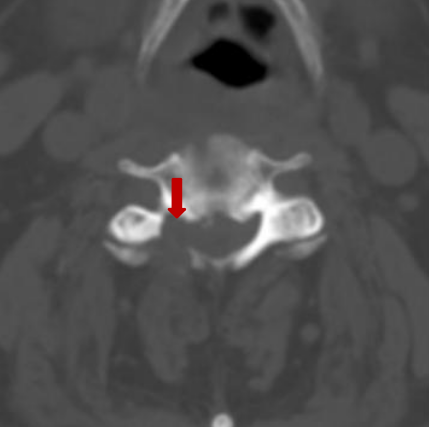

颈前路术后颈椎CT

前入路术后见颈椎间盘突出组织摘除完全。闫先生经住院治疗15天出院,治疗效果非常满意。